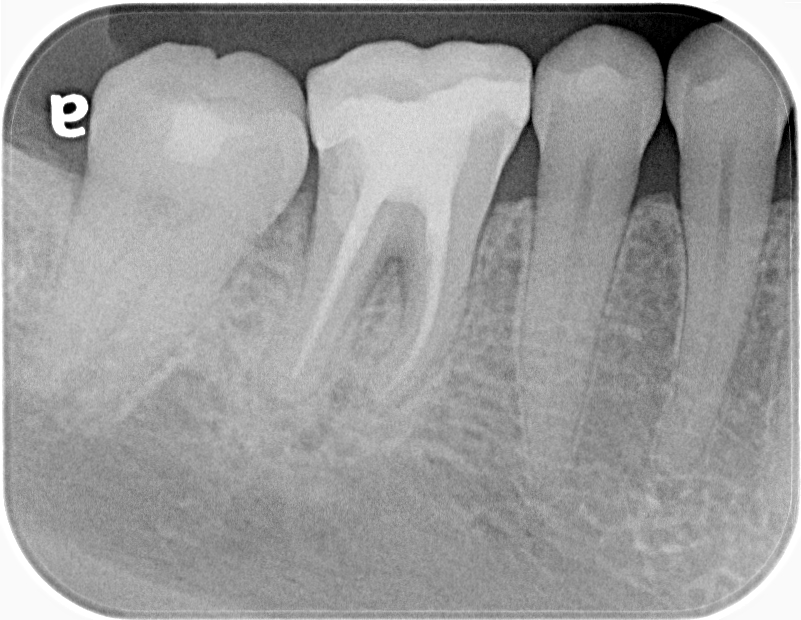

術前の診査では根分岐部に5mm前後のポケットと、透過像を認めます。

術後半年経過を見ましたが、分岐部のポケットと透過像が改善なく排膿を認めたため、歯内歯周疾患と診断し再生療法を行いました。

再生療法を行い術後6ヶ月で分岐部のポケット、透過像の改善が認められました。